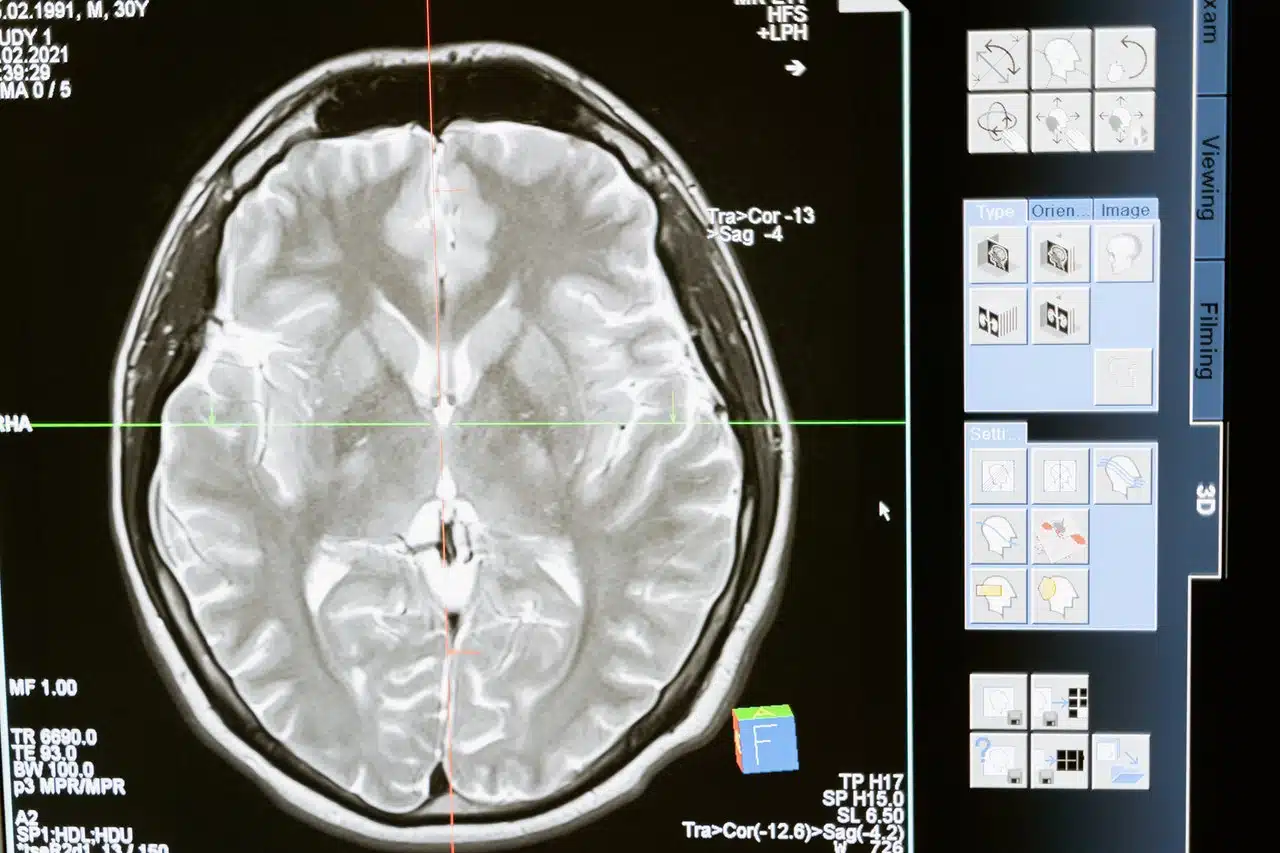

What medical tests help distinguish concussions from TBIs in lawsuits?

Doctors often diagnose concussions through clinical exams and cognitive testing. TBIs may involve imaging tests that show physical damage in the brain. Both types of cases may include additional neurological evaluation.